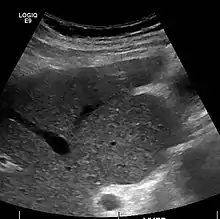

Imaging

Ultrasound is routinely used in the evaluation of cirrhosis.[35] It may show a small and shrunken liver in advanced disease. On ultrasound, there is increased echogenicity with irregular appearing areas.[52] Other suggestive findings are an enlarged caudate lobe, widening of the fissures and enlargement of the spleen.[53] An enlarged spleen, which normally measures less than 11–12 cm (4.3–4.7 in) in adults, may suggest underlying portal hypertension.[54] Ultrasound may also screen for hepatocellular carcinoma and portal hypertension.[35] This is done by assessing flow in the hepatic vein.[55] An increased portal vein pulsatility may be seen. However, this may be a sign of elevated right atrial pressure.[56] Portal vein pulsatility are usually measured by a pulsatility indices (PI).[55] A number above a certain values indicates cirrhosis (see table below).